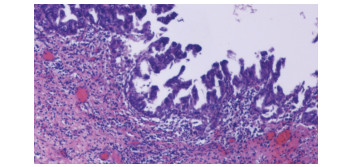

Primary fibrosarcoma of the liver misdiagnosed as hepatic abscess: A case report

Liuyang ZHU, Jiancun HOU, Long YANG, Wen TONG, Yamin ZHANG

2021, 37(7): 1665-1667. DOI: 10.3969/j.issn.1001-5256.2021.07.037

Abstract(896) HTML (266) PDF (3350KB)(81)